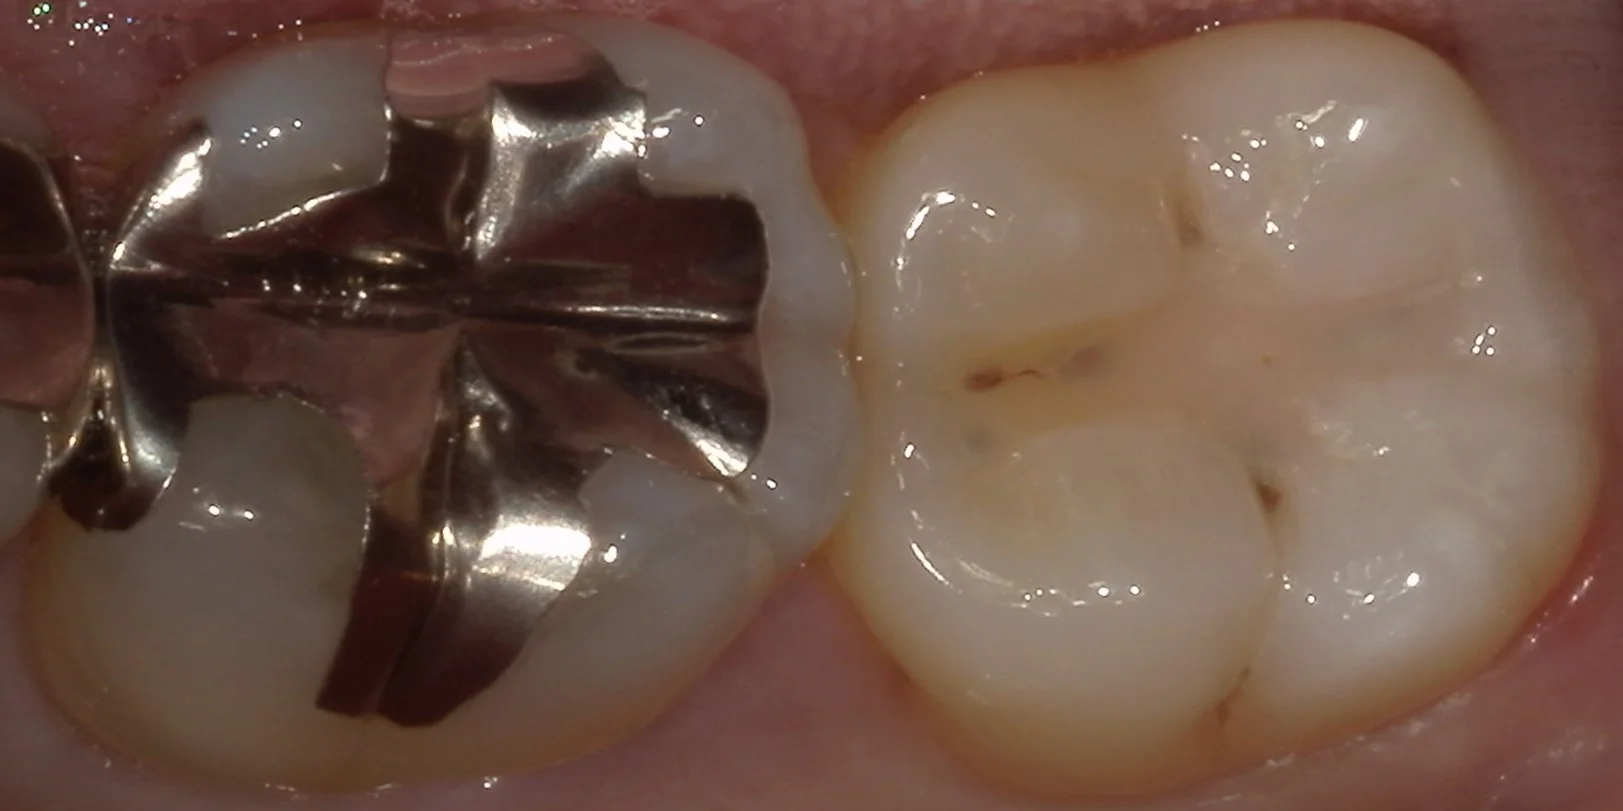

では術前の写真からです。

画像右側の写真が今回治療を行った部分になります。

もともと保険の白い詰め物で治療されていますが、透けて取り残しが見えているというのと、画像の上と下の部分に微小な漏洩が起こっており、そこから内面に大きく虫歯が進行している状態でした。

サイズで行くと非常に小さな虫歯ではありますので、保険診療でもある程度の予後は期待できるかと思われますが・・・

少しでも長く使いたいとのことでしたので、自費診療へと切り替えて治療を行うこととなりました。